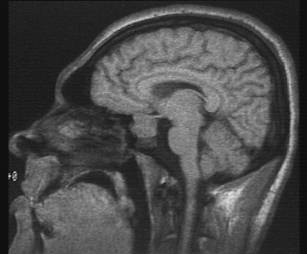

What type of image is it? MRI scans (T1 or T2 weighted)

Which plane the image is in? axial, sagittal or coronal (see

pictures below)

Saggital scan |